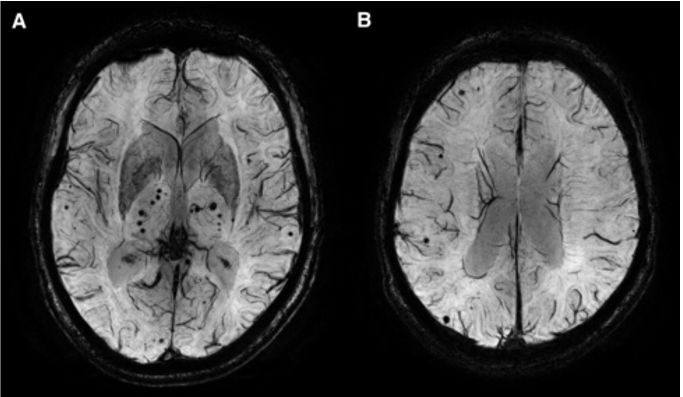

图 CMB患者MRI

SWI图像SWI成像显示:A:为丘脑微出血 B:皮层微出血(上图)